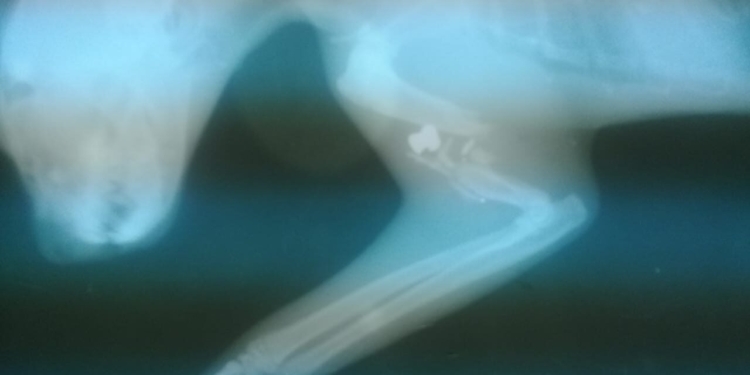

En la radiografía se puede observar claramente el proyectil y cómo quedó el hueso húmero del animal.